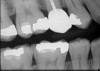

Figure 7 shows the final zirconia crown post cementation. A postcementation radiograph (Figure 8) is essential to ensure that no cement is retained interproximally and to verify accurate margin seating.

Fig 8. Postcementation radiograph.

Figure 8